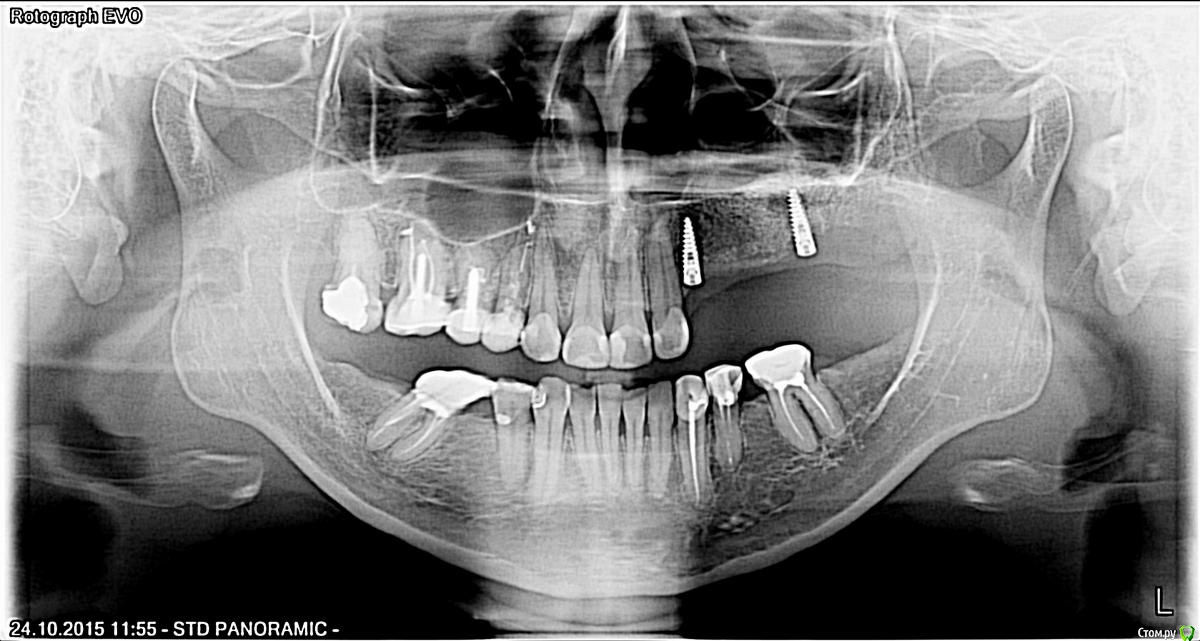

zubovolok Опубликовано 14 декабря, 2015 Поделиться Опубликовано 14 декабря, 2015 Коллеги подскажите пожалуйста как выйти из следующей ситуации - импланты имеют небное положение, узкая платформа, в позиции 2.6 имплант над десной примерно на 3 мм(общая длина 13),импланты mis. Мои техники отказываются делать мк мостовидный протез 2.3-2.6,мотивируя это тем что нужно слишком вестибулярно выводить абатменты и каркас с керамикой, и дистальный имплант оголен и не выдержит окклюзионную нагрузку. Предлагают сделать чспп на шаровидных абатментах, с армировкой. Состоятельна ли будет такая конструкция или на индивидуальных абатментах выводить как то? Ссылка на комментарий

zubovolok Опубликовано 15 декабря, 2015 Автор Поделиться Опубликовано 15 декабря, 2015 (изменено) А как бы он вам поставил вестибулярнее? Только если НКР. и то хз. Я в нёбном положении для протезирования не вижу проблему, ситуацию со складированием пищи на вестибулярном балконе можно решить мягкими тканями если хирург владеет. А вот торчащий на 3 мм имплантат это скорей всего проблема. Ждем снимок. ИМХО. Я не гуру конечно.обещанная панорама Изменено 15 декабря, 2015 пользователем zubovolok Ссылка на комментарий

Evikrol Опубликовано 15 декабря, 2015 Поделиться Опубликовано 15 декабря, 2015 Как на зло всё интегрировалось((( ну хз. Я сам имплантирую, сам себя потом наказываю. Хирургам не понять многих мелочей. Пускай ваш хирург сам отпротезирует, хоть поймёт свою ошибку. Нёбный бугор премоляра будет мешать и дистальный имплантат можно было ближе. Ссылка на комментарий

chervoncevdaniil Опубликовано 15 декабря, 2015 Поделиться Опубликовано 15 декабря, 2015 Да,тоже надеялсся на рентгене увидеть картину не полной интеграции,чтобы можно было обосновать удаление импланта.Не знаю коллега что и посоветовать,если есть возможность корректно отказаться от протезирования и решить вопрос с переустановкой имплантов,то это был бы оптимальный вариант,любое протезирование в этой клинической ситуации-компромис Ссылка на комментарий